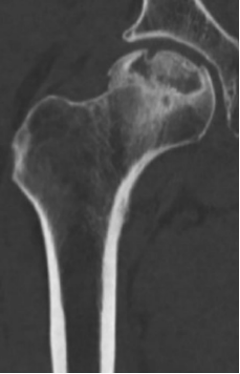

The next patient, a 5-year-old girl (F), had been experiencing consistent hip pain, which was aggravated by physical activities. She had taken an X-ray, which showed that the femoral head of her left hip was slightly flattened. This was diagnosed as avascular necrosis (AVN), more specifically Perthes disease which is a condition in children where blood flow to the femoral head is restricted, causing the bone structure to collapse and leading to a flattened appearance.

Figure 2: Femoral head with AVN.

An MRI scan was considered, but there were risks for such a young patient if they could not remain still, as the anaesthesia used have potential adverse side effects. The outcome of the clinic was to monitor her right hip for possible bilateral involvement. Her parents were advised to limit her activities over the next three months, with an X-ray scheduled in six months, as AVN can sometimes improve on its own over time.